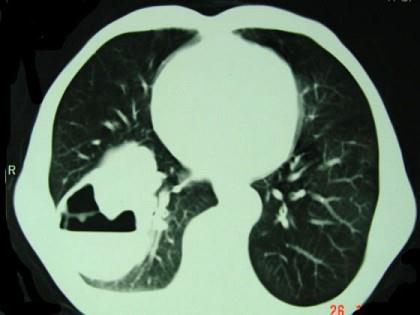

问题 男,76岁,胸痛伴咳嗽,咯血低热一月,CT检查如图,最可能的诊断为 ( )

选项 A、右下肺包虫病 B、右侧包裹性积液 C、右下肺癌伴空洞形成 D、右下肺囊肿 E、右下肺脓肿

答案 C